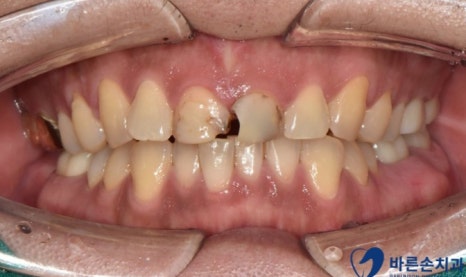

환자분의 경우 육안상으로 보아도 치아의 손상도가 커 보이는데요

정확한 손상 정도를 확인 하기 위해 엑스레이 촬영을 합니다

엑스레이 확인 결과 육안상으로 보는 것 보다

파절정도와 범위가 크고 이로인해 치아의 신경이 노출된 것을 알 수 있었습니다

이런 경우 치아가 많이 손상되어 발치를 생각 볼 수도 있지만

치료 전 후를 비교해 볼까요?

치료전 치료후